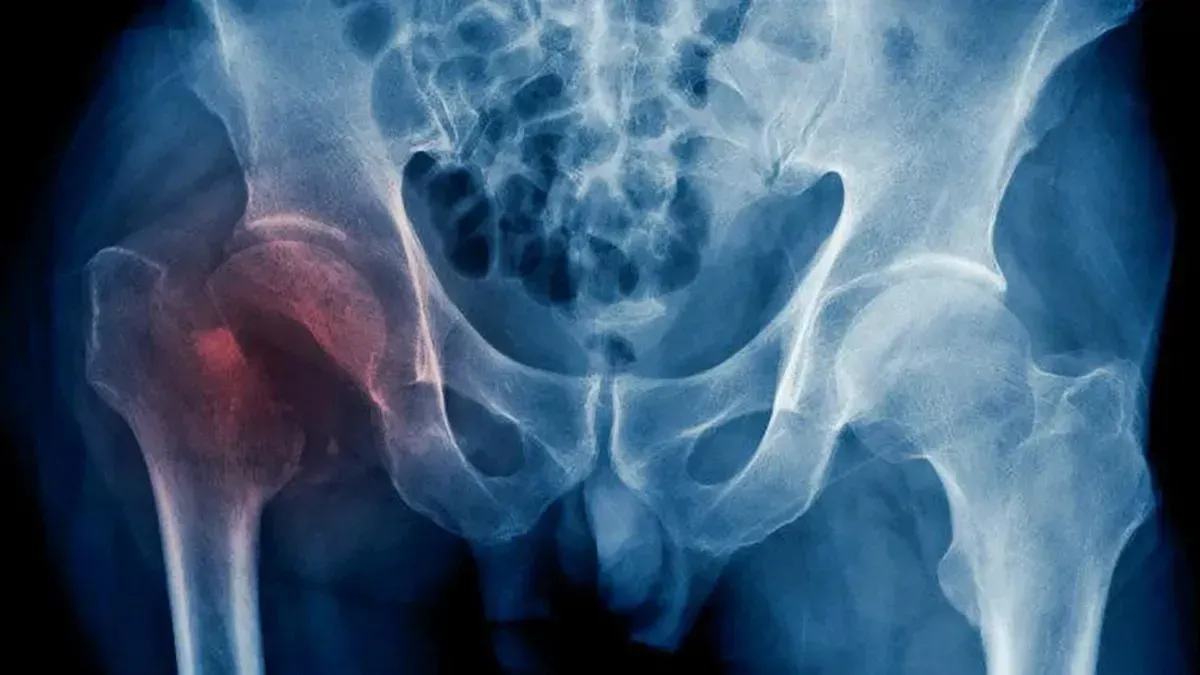

La osteoporosis es una enfermedad silenciosa que no presenta síntomas. Esta afecta a nuestros huesos, que se vuelven más porosos y frágiles. Como consecuencia, se produce una pérdida de masa ósea que genera fracturas en este tejido.